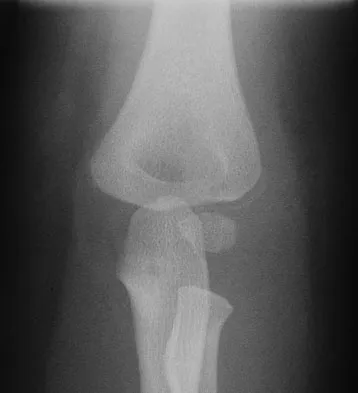

Figures 9a and 9b show the radiographs of a 4-year-old child who sustained an elbow injury. What is the most likely complication resulting from this fracture if treated in a cast?

The radiographs show a lateral condyle fracture with 2 mm of displacement. As opposed to other pediatric elbow fractures, lateral condyle fractures have a higher incidence of nonunion. This may be due to minimal metaphyseal bone on the distal fragment, the intra-articular nature of the fracture, or from further displacement when treated nonsurgically. These fractures with 2 mm and greater of displacement should be treated with reduction and stabilization. Osteonecrosis and fishtail deformity may be seen in very rare cases of lateral condyle fractures. The incidence is certainly less than the rates of nonunion seen in nonsurgically treated fractures with 2 mm and greater of displacement. Varus malunion from overgrowth and elbow stiffness are more likely seen in fractures treated surgically. Pirker ME, Weinberg AM, Hollwarth ME, et al: Subsequent displacement of initially nondisplaced and minimally displaced fractures of the lateral humeral condyle in children. J Trauma 2005;58:1202-1207. Finnbogason T, Karlsson G, Lindberg L, et al: Nondisplaced and minimally displaced fractures of the lateral humeral condyle in children: A prospective radiographic investigation of fracture stability. J Pediatr Orthop 1995;15:422-425.